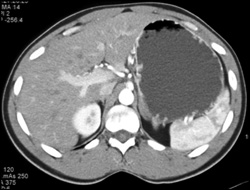

Venous Collaterals Around Stomach